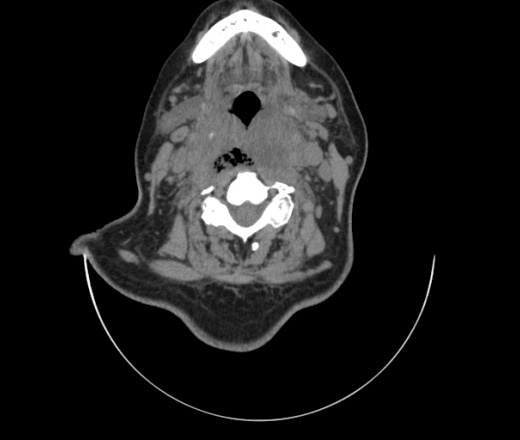

Женщина поступила в х/о спустя 4 дня после того как при употреблении карася подавилась костью.

Наличие газа в средостении на протяжении тел С2-С6 (медиастинальна эмфизема); рыбная кость на уровне тела С6.

При всем уважении, но говорить о медиастинальной эмфиземе, оценивая мягкие ткани шеи, как-то слишком резко. На мой взгляд, это ретрофарингеальное пространство.

Согласен с Вами; конечно, наличие газа в клетчатке ретрофарингеального пространства (затмение с опечаткой..). К сожалению, процесс "продвигается" к медиастиниту. Но почему никто, не отмечает наличие рыб. кости; или это для Всех очевидно?

Кость то мы сразу выявили, размеры где то 17*2мм, но ее так и не получается найти в этой каше